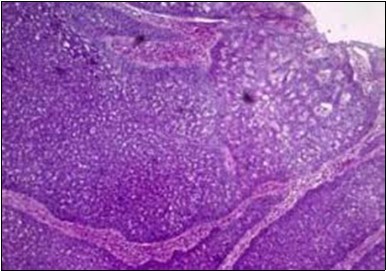

Figure 1.Solid aggregates of tumour cells and duct structures in eccrine porocarcinoma (14).

Solid aggregates of tumour cells and duct structures in eccrine porocarcinoma (14).